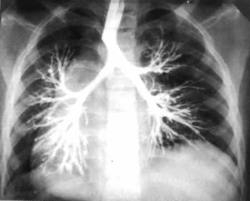

Диагностика бронхоэктазий основывается на анамнестических данных, особенно первого года жизни, и симптоматике, которая может быть различной в зависимости от распространенности процесса. Окончательный диагноз ставят только после полного клинического бронхиального обследования: бронхоскопии, рентгенографии, бронхографии и радиоизотопных методов исследования. Мокроту исследуют с целью установления микрофлоры, в некоторых случаях — для выявления туберкулеза. Ангиографию применяют по ограниченным показаниям ( когда подозревается легочная гипертензия). В детском возрасте часто встречаются комбинированные поражения, когда имеются, например, бронхоэктазы одной доли и сегментов — другой.

Медицинские процедуры, проводимые при заболевании бронхоэктазы у детей (расширение бронхов): Клинический анализ крови, Бронхоскопия, Ангиопневмография, Рентгенография легких, Бронхография, Радиоизотопное исследование, Исследование мокроты